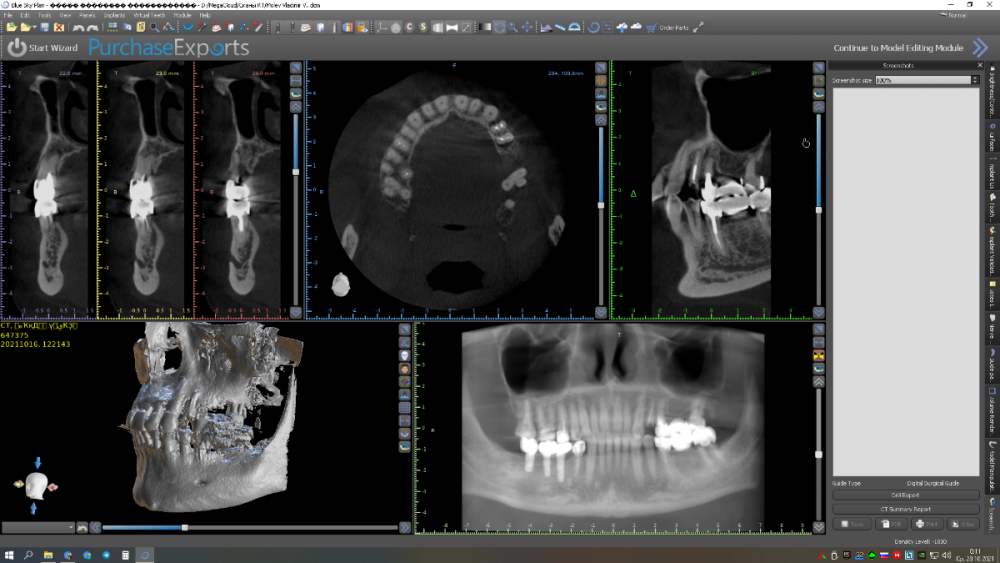

Женька Опубликовано 11 января, 2022 Автор Поделиться Опубликовано 11 января, 2022 Как я и говорил? купил объектив, теперь буду больше своих косяков фотографировать и выкладывать. Наконец-то руки дошли и машина доехала обратно до Башкирии и прооперировал пациента. Аккуратно сняли мост путём отпиливания по коронкам, удалили зубы достаточно быстро. Долго ловил пилотной фрезой дентиум правильное положение... так и не поймал. Вспомнил как Пётр Лазукин использует фрезу на турбинке для пилотного сверления и о чудо, сразу появилось устойчивое направление и линдеман перестал соскакивать, спасибо за видосики Петру Ну и далее по протоколу, пилотное положение 2.4 и 2.5 менял по 3 раза каждый (а в итоге всё равно не доволен получившимся направлением и судя по всему слишком близко) 2.7 с синуслифтингом. В лунки A-oss, сверху мембрана от Владмивы. И заживление через 9 дней. К сожалению, фото швов и той порнографии, что была сделана с лунками и мембраной нет. Резюмируя, это были 35-38 имплантаты которые я поставил, я уже чувствую себя намного увереннее (когда как Пётр турбиной пилотную точку сделал вообще в себя поверил ), но проблемы с позиционированием ещё долго будут меня преследовать. Жду критику и помидоры за РГ контроль. Ссылка на комментарий